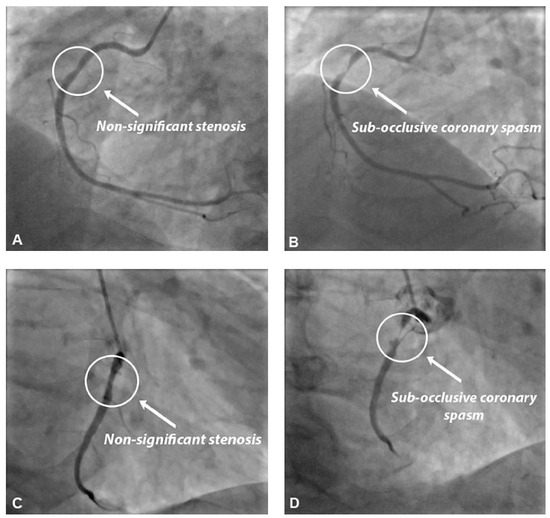

Vasospastic angina is a clinical disorder primarily attributable to coronary artery spasm and typically characterised by a history of rest angina that promptly responds to short-acting nitrates. In this case report, we describe a 72-year-old man affected by vasospastic angina, who presented with asymptomatic transmural ischaemia during a routine exercise stress test and paradoxical subocclusive coronary spasm, superimposed on a non-significant coronary stenosis, following intracoronary nitroglycerin injection during coronary angiography. Other cases of paradoxical vasospastic response to nitrates during coronary angiography have been already described in literature. However, in these previously described cases, coronary spasm occurred in a portion of the vessel close to the catheter tip or following sublingual nitroglycerin administration, thus making it difficult to clearly assess the possible causative relation between nitrate administration and coronary spasm. This represents, to the best of our knowledge, the first described case of paradoxical coronary spasm occurring a few seconds after direct intracoronary nitroglycerin injection and in a portion of the vessel far enough from the catheter tip to exclude late-onset catheter-induced spasm in the absence of any catheter-tip drop-in or deep intubation. A paradoxical vasospastic response to nitrates in vasospastic angina patients represents a rare but very challenging condition. Thus, the best therapeutic approach in this subgroup of patients remains unclear. In our patient, because of the transmural ischaemia documented during the exercise stress test, a percutaneous coronary intervention (PCI) was performed and the clinical evolution was favourable. Therefore, we believe that PCI might represent an effective therapeutic option in vasospastic angina patients with a paradoxical response to nitrates and focal epicardial coronary spasm. Full article

Figure 1